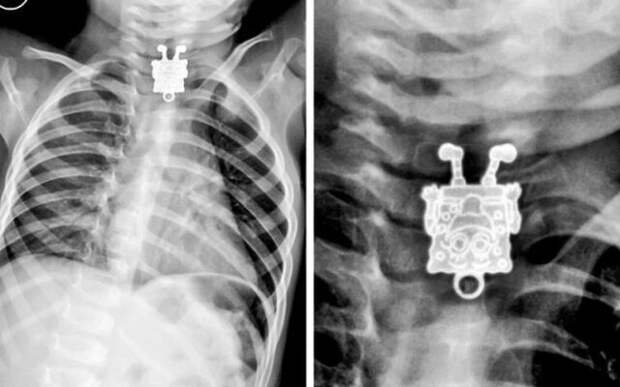

Панорамный снимок лицевого черепа  16-месячный мальчик проглотил Спанч Боба

16-месячный мальчик проглотил Спанч Боба